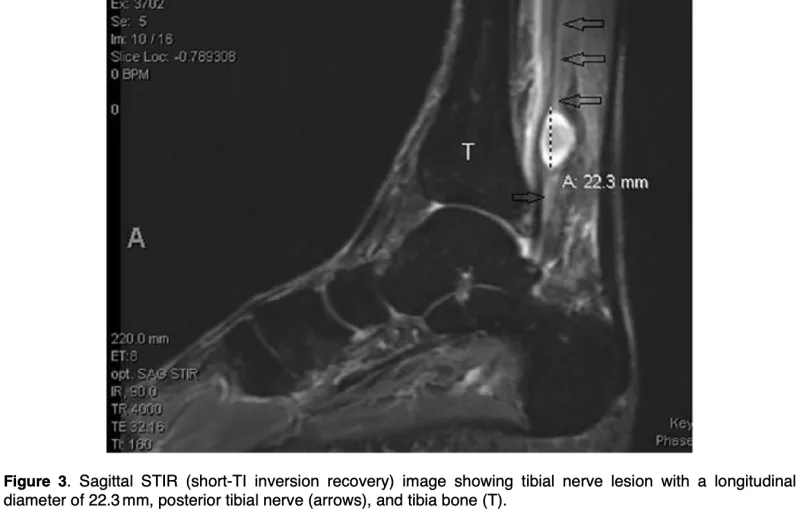

足関節の内くるぶし後方に3 cm大の腫瘤を認め, 軽く叩くと踵に電気が走るように響くような痛みが出ました.

引用元:Daniel M. Posterior tibial nerve schwannoma in a multiple myeloma patient: A case report. SAGE Open Med Case Rep. 2019. 7.

MRIでは, アキレス腱の内側奧, 脛骨神経に腫瘍を認め, 脛骨神経の神経鞘腫と診断しました.

早期の手術をご希望され, 今月中に手術を行うように予約しました.